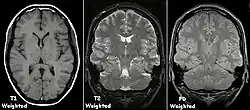

Ein Gehirn in T1-, T2- und PD-Wichtung

Zum besseren Verständnis wird hier das Prinzip der grundlegenden (1950 von Erwin Hahn erfundenen) Spinecho-Sequenz kurz skizziert. Eine „Sequenz“ (auch „Pulssequenz“) ist in diesem Zusammenhang eine Abfolge von Hochfrequenz- und magnetischen Gradientenfeldern (in drei orthogonalen Orientierungen), die vielfach in jeder Sekunde in vorgegebener Reihenfolge ein- und ausgeschaltet werden.

Um eine -gewichtete Aufnahme zu erhalten, setzt man den Rephasierungsimpuls relativ spät, so dass die Spin-Spin-Relaxation Zeit hat, sich auszuwirken; man spricht von einer langen Echozeit TE (). Auch der zeitliche Abstand bis zur nächsten Messung ist sehr lang, damit die (maximale) longitudinale Ausgangsmagnetisierung durch die Spin-Gitter-Relaxation in allen Geweben weitestgehend wieder erreicht wird. Man spricht von einer langen Repetitionszeit TR (). Mit langer TE und langer TR bekommt man helles Signal nur von Geweben mit langer -Zeit. Für eine -Wichtung braucht man umgekehrt kurze TE () und kurze TR (), dann überwiegen die unterschiedlichen Spin-Gitter-Relaxationen verschiedener Gewebe im Bildkontrast. Eine Sequenz mit kurzer TE () und langer TR () erzeugt einen Kontrast, der sich überwiegend nach der Konzentration der Protonen im Gewebe richtet, die praktisch der Anzahl der Wasserstoffatome entspricht; dies ist die sogenannte Protonendichte-(PD-)-Wichtung. Es gibt zahlreiche Weiterentwicklungen dieser einfachen Spinecho-Sequenzen, etwa zur Beschleunigung oder mit Unterdrückung des Fettgewebesignals. Eine klinische MRT-Untersuchung umfasst unterschiedlich gewichtete Bildserien und mehrere räumlichen Ebenen.

Je nach Gewichtung kommen die verschiedenen Gewebe in charakteristischer Intensitätsverteilung zur Darstellung:

• In der T1-Wichtung (T1w) erscheint Fettgewebe hyperintens (signalreich, hell) und damit auch fetthaltige/-reiche Gewebe (z. B. Knochenmark). Diese Gewichtung eignet sich daher gut zur anatomischen Darstellung von Organstrukturen und insbesondere nach Kontrastmittelgabe (Gadolinium) zur besseren Abgrenzbarkeit unbekannter Strukturen (z. B. Tumor).

• In der T2-Wichtung (T2w) erscheinen stationäre Flüssigkeiten hyperintens, so dass flüssigkeitsgefüllte Strukturen (z. B. Liquorräume) signalreich und damit hell erscheinen. Dadurch eignet sich diese Gewichtung zur Darstellung von Ergussbildungen und Ödemen sowie z. B. zur Abgrenzung von Zysten gegenüber soliden Tumoren.

• Protonendichte-gewichtete (PDw) Bilder sind flau (weniger Gewebekontrast), aber scharf. Knorpel kann sehr detailliert beurteilt werden. In Verbindung mit einem Fettsättigungsimpuls gehören PDw-Bilder deshalb zum Standard in Gelenkuntersuchungen.